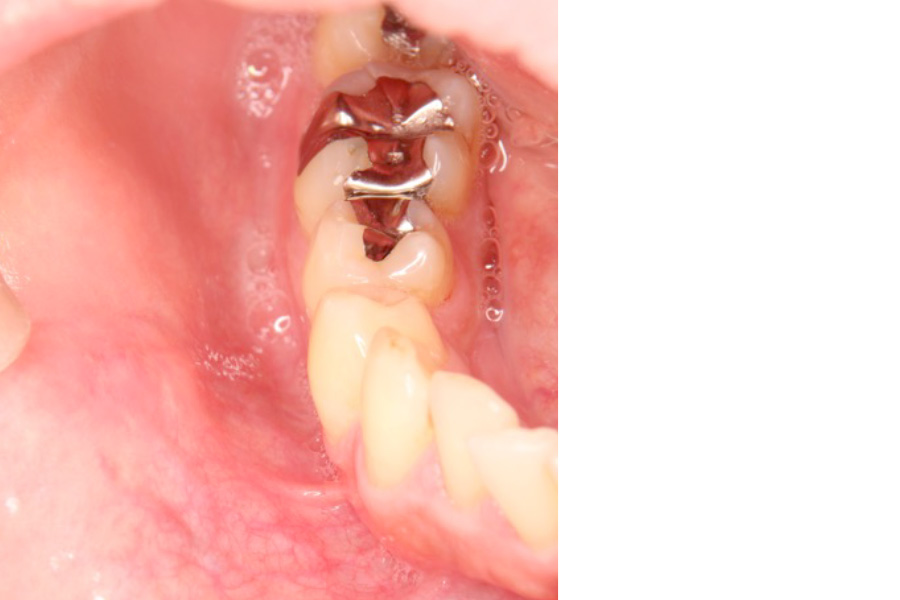

- 頬粘膜に発生した粘液貯留嚢胞を外科的に切除しました。

局所麻酔下で嚢胞とその原因となっている唾液腺組織を丁寧に除去し、再発を防ぐために粘膜下をきれいに処理しました。

手術後は軽度の腫れがみられましたが、経過良好で再発はありませんでした。